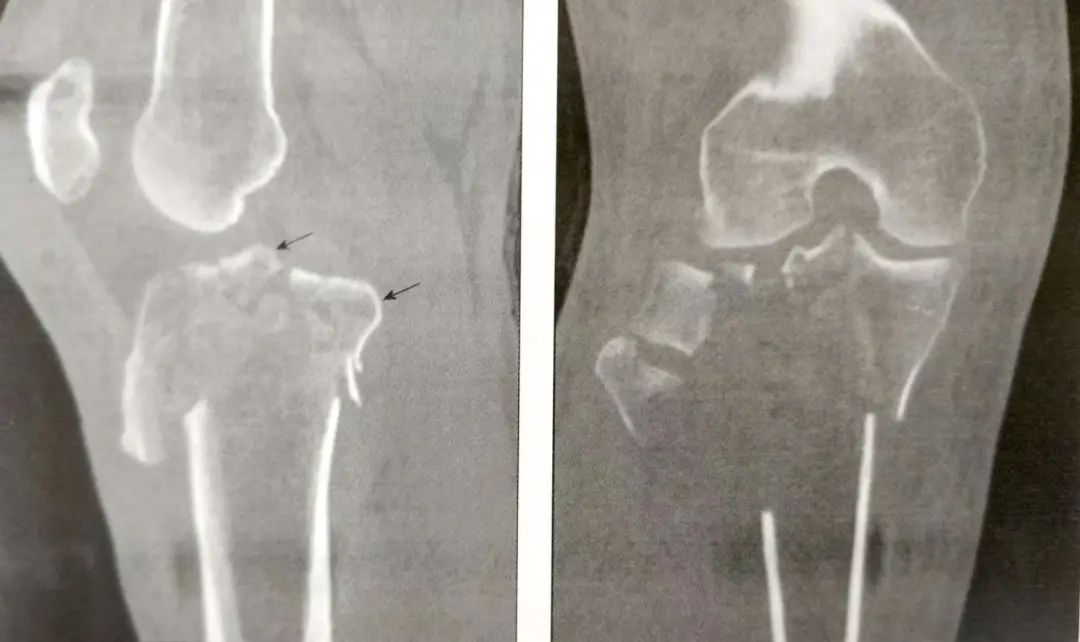

A:前交叉韧带撕脱骨折(箭头)

B:后交叉韧带胫骨附着点撕脱骨折

▲前外侧髁间嵴骨折(箭头)